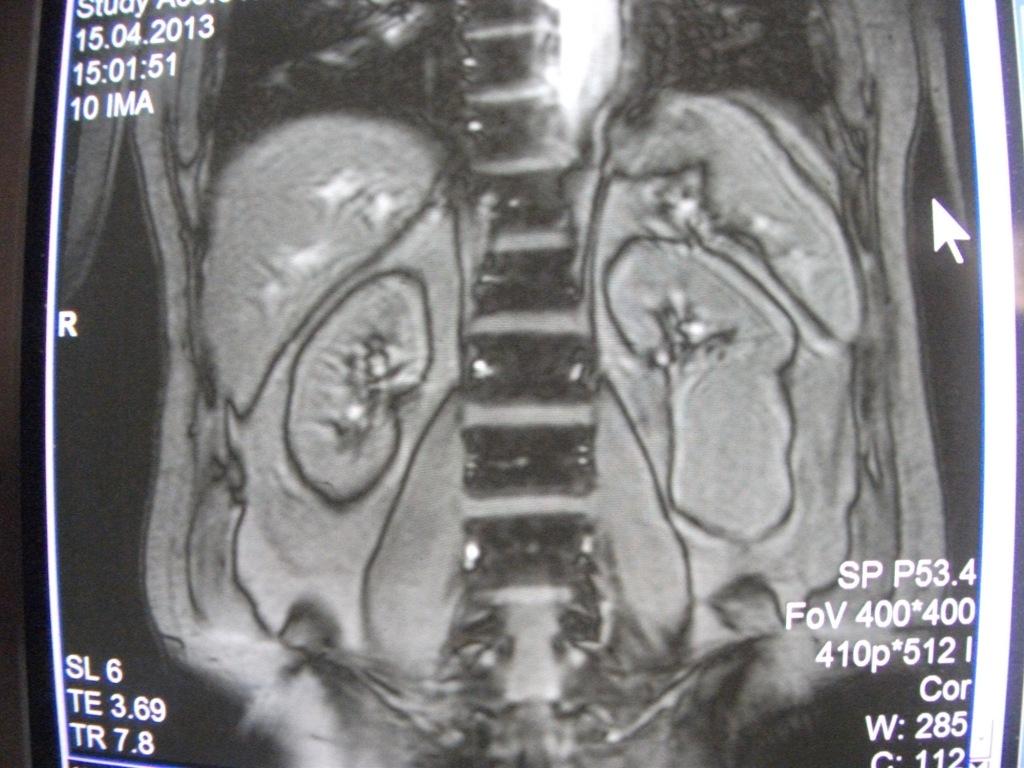

такое заключение: Левая почка: расположена обычно, увеличена, общими размерами около 13х5,5см. В области средней и нижней трети почки определяется объёмное образование неправильной формы, деформирующее наружный контур почки, распространяющиеся с чашечно-лоханочную систему. Опухоль имеет четкие неровные бугристые контуры с наличием псевдокапсулы, неоднородной структуры с признаками распада, максимальными размерами около 78,7х47х48мм

Вопрос такой: можно ли обойтись без удаления почки, удалив только опухоль.

Технически можно. Но практически - лучше нефрэктомия.